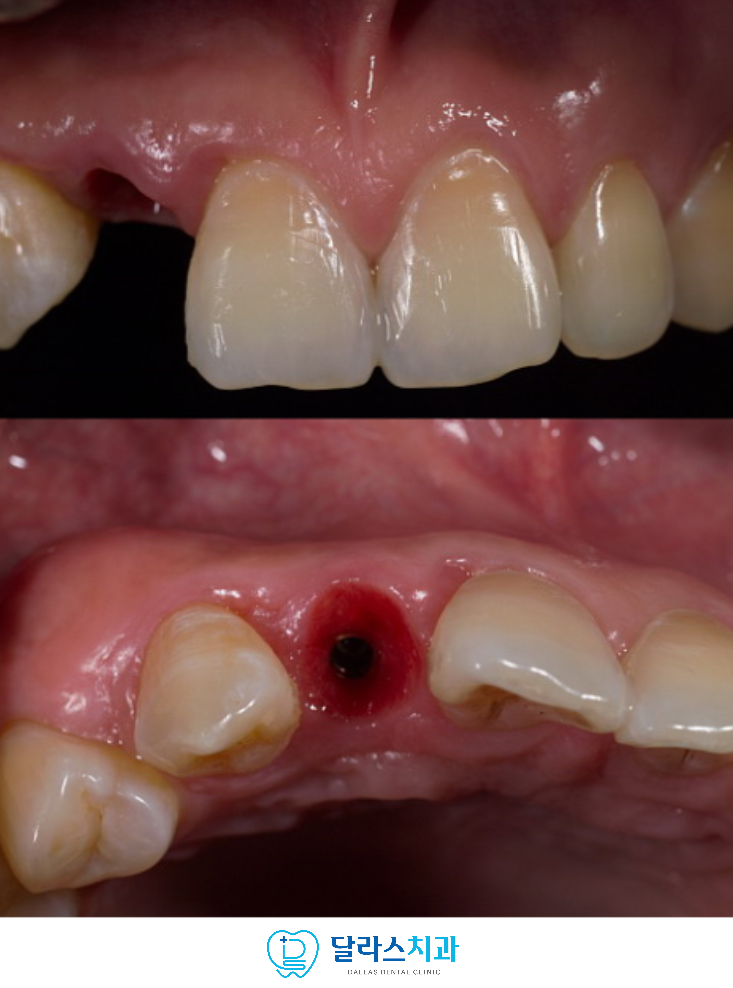

임플란트 식립까지 완료한 후에는 임시 치아를 장착하여

잇몸 라인을 자연스럽게 형성하였습니다.

이 과정을 통해 최종 보철물이 인접 치아와

조화롭게 자리잡을 수 있도록 기반을 마련했습니다.